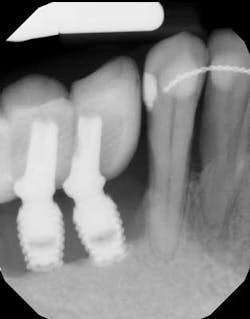

Approximately 30,000 people in Sweden receive dental implants each year, and Sweden is among the countries with the most dental implants per capita. (1) Given that almost 8% of patients lose at least one implant within 10 years (1) and more develop severe complications such as peri-implantitis, Derks’ study aimed to shed some light.

Files of 2,765 patients were gathered from more than 800 clinicians. Information about these patients, treatment procedures, and outcomes related to the implant-supported restorative therapy was pulled from the files, and 596 of the patients attended a clinical exam nine years following therapy. What makes this study unique is that it analyzes biological complications such as peri-implantitis, where previous studies were often limited to observing patient populations in specialty care. (1)

Studies have demonstrated very high, long-term survival rates for dental implants; however, like any other dental treatment, success rates depend on a variety of factors. People have problems with and lose dental implants for the same reason people lose teeth. Smoking, diabetes, poor oral hygiene, infrequent cleanings, and uncontrolled periodontal disease have all been shown to be associated with implant complications. To think that implants would be immune from these factors when we have seen their detrimental effects on teeth is foolish.